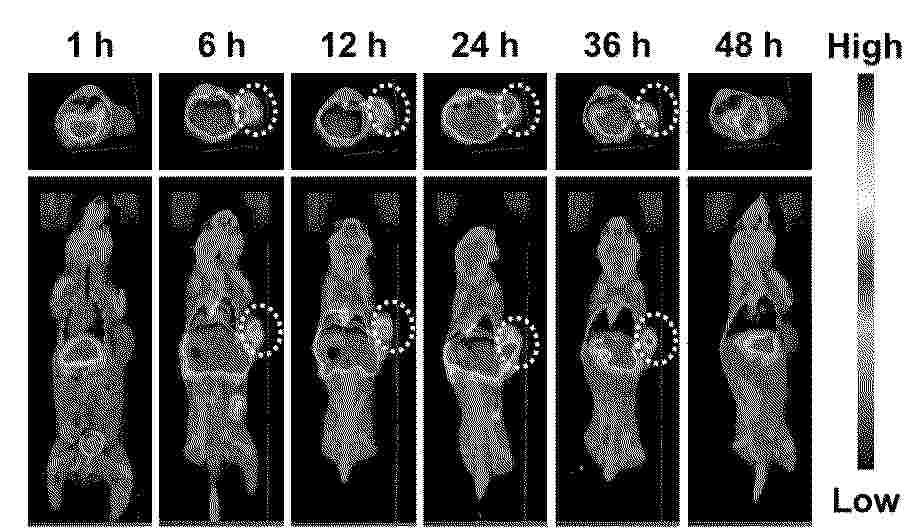

Radioiodine-labeled drug-loaded bacterial outer membrane vesicle, preparation method and application

Resumen de: CN120324371A

The invention relates to a radioiodine-labeled drug-loaded bacterial outer membrane vesicle as well as a preparation method and application thereof, and belongs to the technical field of biological medicines. The preparation method comprises the following steps: expressing casein-rich attenuated salmonella typhimurium VNP20009 to secrete bacterial outer membrane vesicles, loading an anti-tumor drug by using an ultrasonic method, and combining with an oxidant-mediated radioiodine labeling technology to construct radioiodine-labeled drug-loaded bacterial outer membrane vesicles with tumor targeting property, so as to prepare the drug-loaded bacterial outer membrane vesicles. The performance is optimized through polyethylene glycol modification, the drug loading mass ratio is controllable, the radiolabeling rate is high, the in-vitro stability is good, and the in-vivo safety is good. The drug-loaded bacterial outer membrane vesicle can simultaneously realize SPECT/PET imaging and targeted therapy, is suitable for solid tumors such as brain glioma, colon cancer and the like, has the functions of drug delivery, immune activation and radiodiagnosis, has a good application prospect, and provides a new tool for diagnosis and treatment of tumors.